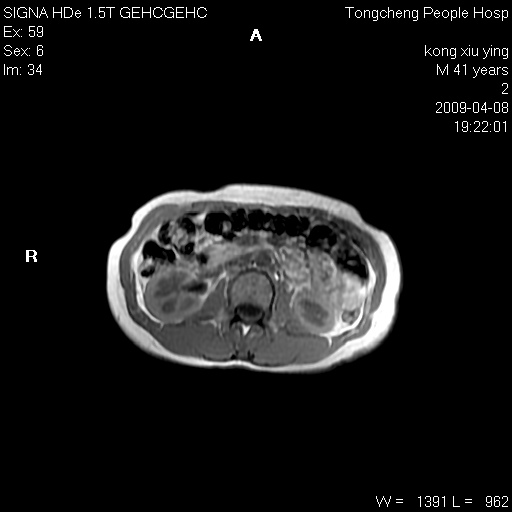

标题: CL1008:【经典】胆囊石榴籽样结石。 [打印本页]

标题: CL1008:【经典】胆囊石榴籽样结石。

女,41岁。健康体检——彩超提示:胆囊显示不清。平素健康,无不适感。

腹部mr扫描及mrcp,图像如下:

胆囊石榴籽样结石。